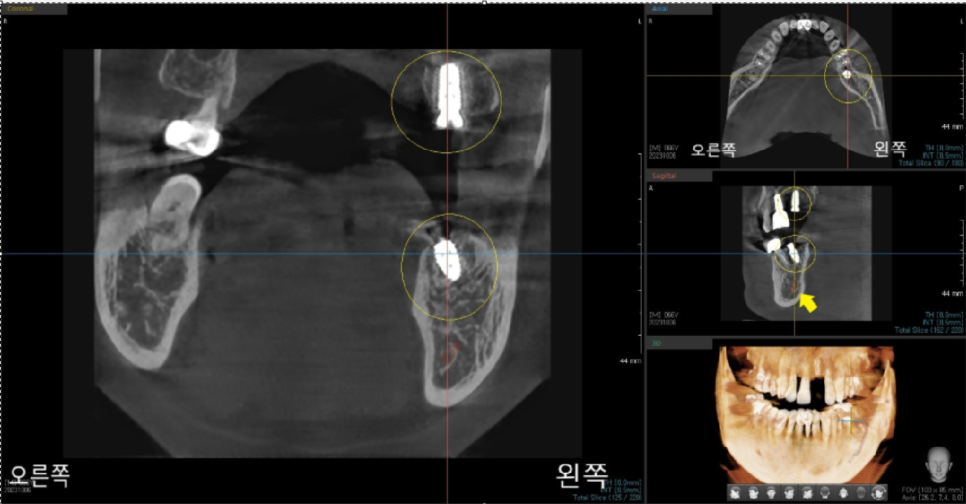

저희 바르디 치과에서는

임플란트 수술 후에도 3D CT를 촬영하여

임플란트 식립 위치가 올바르게 되었는지

확인해 드립니다.

임플란트의 윗부분에 지대주 어버트먼트가 들어가게 되는데

기성 어버트먼트가 아닌

맞춤 커스텀 어버트먼트가 들어가게 됩니다.

커스텀 어버트먼트는 환자분의 임플란트 위에

치주의 생김새와 상부 보철을 고려한 어버트먼트입니다.

맞춤 정장을 생각하시면 쉬우실 겁니다.